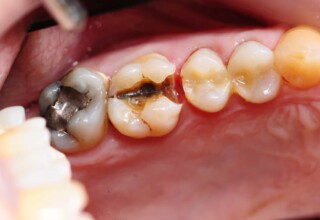

Restoration of a cracked molar with composite resin

Cracked teeth present a challenge in restorative dentistry both from the aspect of complexity of the restoration itself (usually large filings) and the necessary providings to avoid a complete fracture. The presented case demonstrates the simplest approach of a bonded direct restoration with composite resin. It is based on the principle of an adhesive filling that “holds” the remaining tooth structures “together”. The restored molar remained healthy for two years, then required a root canal and a crown was placed for maximum protection.